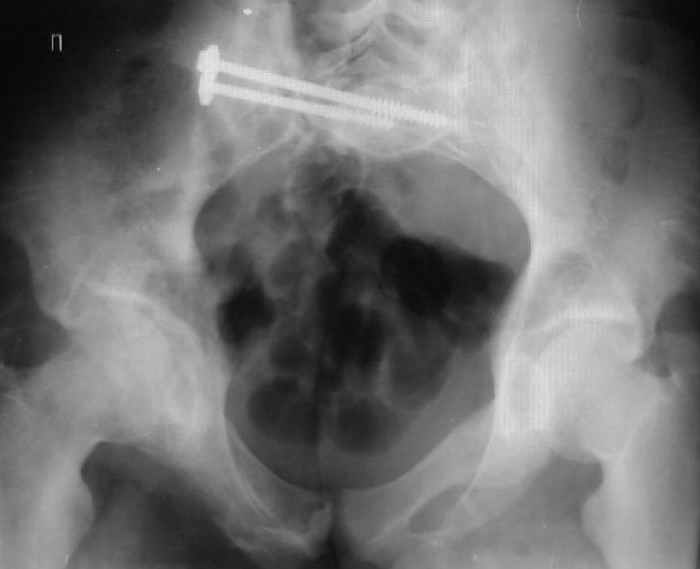

Для информации к размышлению о возможности исправления имеющейся деформации предлагаю похожий случай.